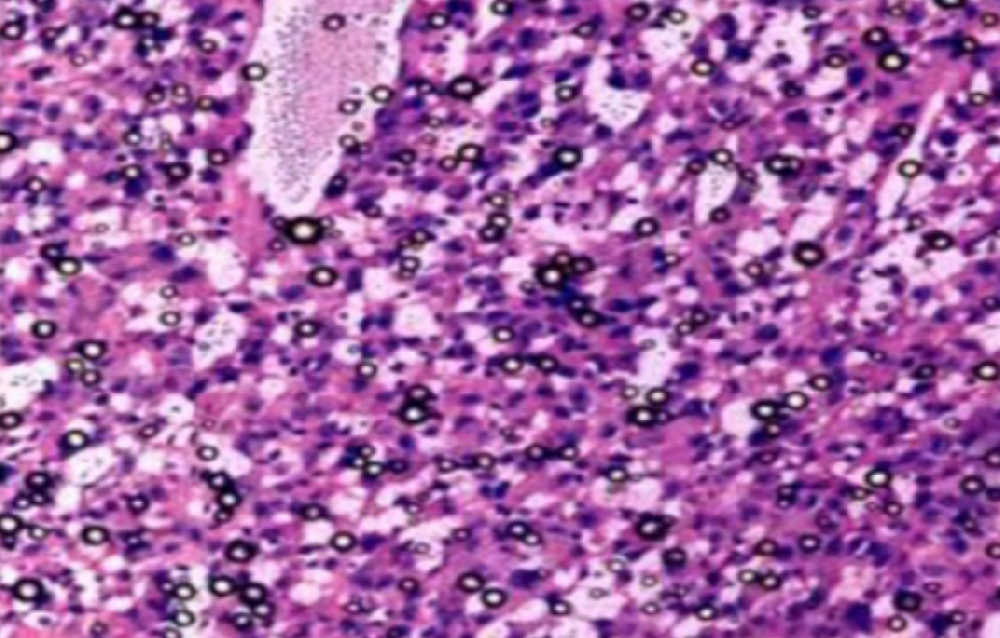

①常规HE染色,切片厚度需要根据不同组织类型而定。

②光镜下首先区分有否特异性病变及范围,然后由脏器一端向另一端进行整体观察和描述。

③观察小动物脏器有否肿大、增生,用10倍镜由一端开始计数该脏器包含的10倍镜镜头视野数,或计数整个切片中功能单位数。如脾生发中心、胸腺小叶、肝小叶、肾小球及整个切片中病变灶数量。

④大动物脏器疑有肿大、增生时,用40倍镜头计数每一视野中的细胞或功能单位数。心肌、骨骼肌在与长轴平行的切面上计数每一视野直径中的肌纤维数、肝小叶中肝细胞索数(数40倍镜视野的一半)。根据需要计数10~20个40倍镜视野。

⑤确定病灶大小后用40倍镜头进行观察。先将镜头的圆周与观察的病灶边缘相切,再观察该病灶在这一视野中的比例。

⑥实验动物肿瘤发生率的计算:动物肿瘤的组织分化常常不明显,在长期毒性试验或诱癌实验中出现的肿瘤,不论良性还是恶性,均计入肿瘤发生数,并计算肿瘤发生率。